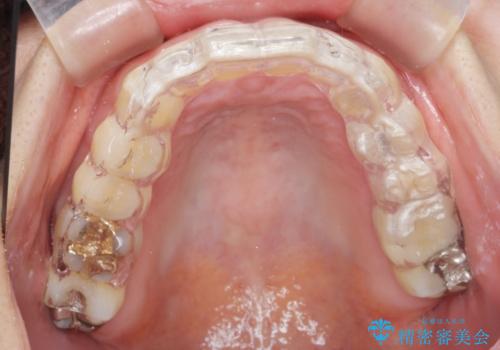

ナイトガードによる歯の予防

- 食いしばりがひどくてセラミックの被せ物が欠けたとの事で来院。

欠けたセラミックを新しいセラミックに変えた後、今後欠けたり割れたりしないように

ナイトガード(自費)を作製しました。

保険のナイトガードに比べて自費のナイトガードは割れる心配がないです。

また噛み合わせの歯と調整をして全体に均一に当たるように調整を行うので噛んだとき力が全体的に分散して歯の負担も減ります。